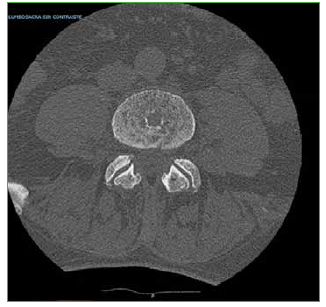

Las hernias discales intraesponjosas vertebrales o nódulos de Schmörl consisten en una herniación o una extrusión del núcleo pulposo del disco intervertebral a través del platillo vertebral hacia el cuerpo adyacente. Suelen asociarse a deformidades vertebrales, como la enfermedad de Scheuermann, o a enfermedades reumáticas, como la espondilitis anquilopoyética. En general, son hallazgos casuales y cuadros asintomáticos; son pocos los casos publicados de nódulos sintomáticos. Su aparición estaría relacionada con un platillo vertebral debilitado por traumatismo o estrés repetido. Cuando el nódulo es agudo o reciente, puede ser difícil diferenciar la degeneración benigna de una infiltración maligna o una infección. Presentamos un caso inusual de un nódulo de Schmörl doloroso en un hombre sin antecedentes de relevancia, que enmascaró una lesión metastásica de carcinoma pancreático a nivel lumbar. Se realiza una revisión bibliográfica. ABSTRACTIntraosseous disc herniation –or Schmörl nodes (SN)– are a herniation or prolapse of the nucleus pulposus of the intervertebral disc through the vertebral plate and into the adjacent vertebral body. They are usually associated with vertebral deformities, suchas Scheuermann’s disease, or rheumatic diseases, such as ankylopoietic spondylitis. In general, they are spontaneous and asymptomatic findings, and there are only a few reported cases of symptomatic nodes. The etiology is supposedly related to a weakened spinal plate due to trauma or repeated stress. When the node is acute or recent, it can be difficult to differentiate a benign degeneration from a malignant infiltration or infection. In this paper, we discuss the unusual case of a painful Schmörl node in a man with no relevant history and a masked metastatic lumbar spinal tumor originated from pancreatic cancer. We performed a literature review.Descargas